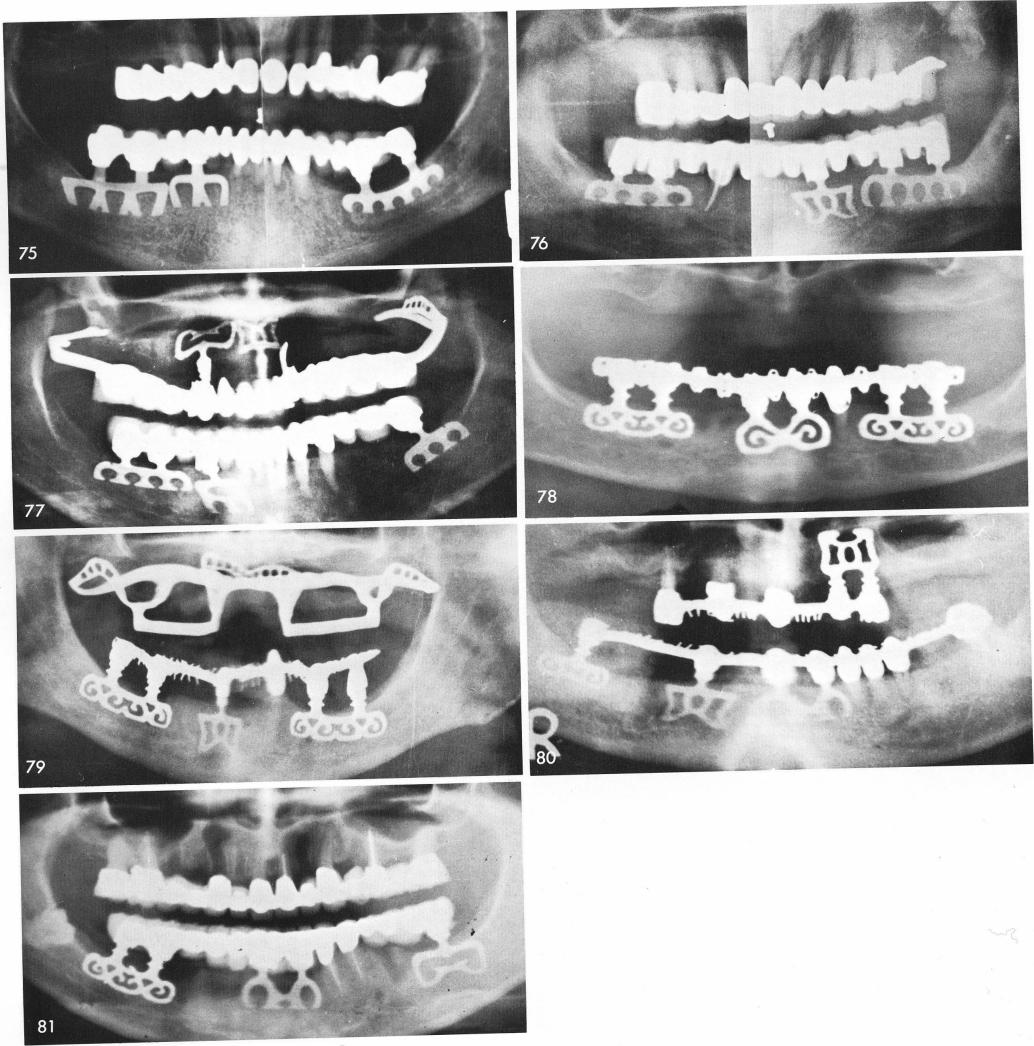

Mandibular Implants (published 1977)   Dr. Leonard I. Linkow